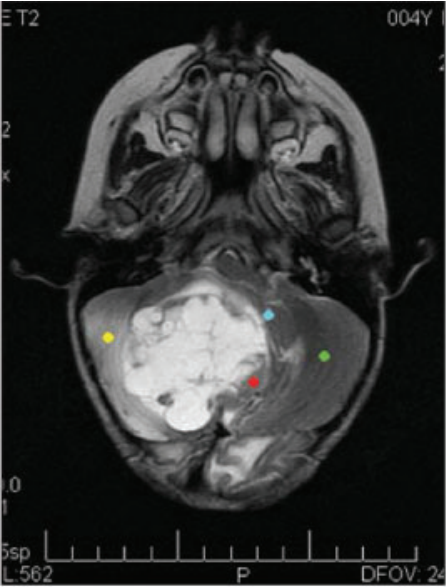

Para investigação de tumores da fossa posterior, foi obtida a seguinte imagem:

Adaptado de Santos et al., 2004.

A referida imagem corresponde a: